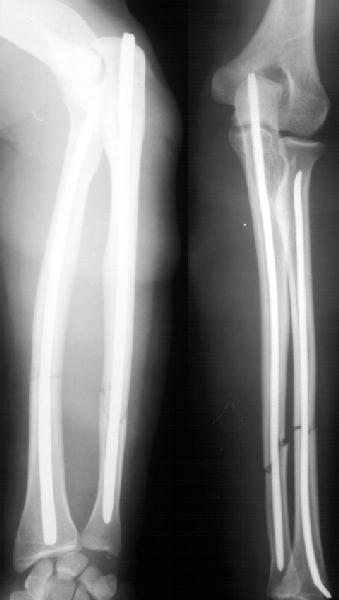

А движения как раз начинаются максимально рано, на следующий день, включая ротацию - больших ран ведь нет, сильно не болит - в приложении картина в день снятия швов.

К месяцу после операции практически у всех больных - клиническая картина здорового человека.

Так что стабильность достаточная. А то, что она не абсолютная, как с пластинкой - это как раз способствует периостальному сращению. Конечно, при многооскольчатых переломах для осевой устойчивости лучше запирать винтами.